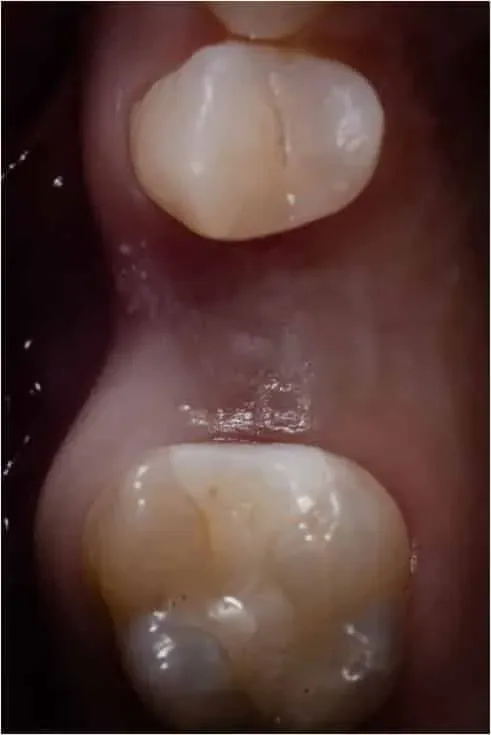

Prossimità di denti umani con un impianto nel mezzo

Corona su impianto dopo lembo a riposizionamento laterale e sutura a materassario a 360 gradi